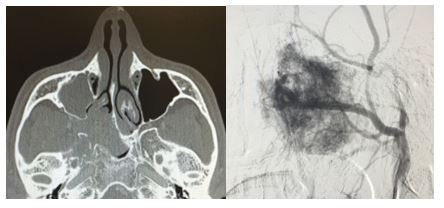

4. 03/2018. Masculino 16 años con obstrucción nasal de inicio gradual, epistaxis recurrente izquierda, masa la cavidad nasal bilateral y abombamiento de paladar blando de 3 años de evolución. TC y RM con extensión a seno maxilar izquierdo fosa infratemporal, fisura infraorbitaria e intracraneal izquierdo. Clasificación IIIA (Radkowski) IV (Chandler). Se realiza angiografía, embolización y resección vía Degloving, con resección completa de tumor, buena evolución posquirúrgica a 6 meses, sin recurrencia.